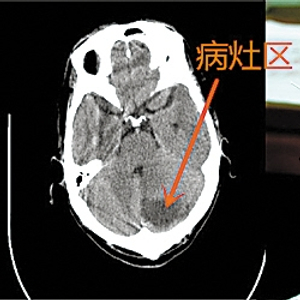

患者CT片中的病灶区&围针的部位

操作方法:患者先接受CT检查,医生根据CT片来定位中风患者的病灶,然后对病灶在头皮的特定投射区(最近距离投射区)周边进行围针治疗中风。用针的多少根据病灶大小而定,数量4到8根不等,并依病灶形状不同而进行椭圆形、圆形、不规则形围针。和传统头针相比,CT或MR定位围针法取穴则直接针对病灶,刺激更全面,疗效更肯定。